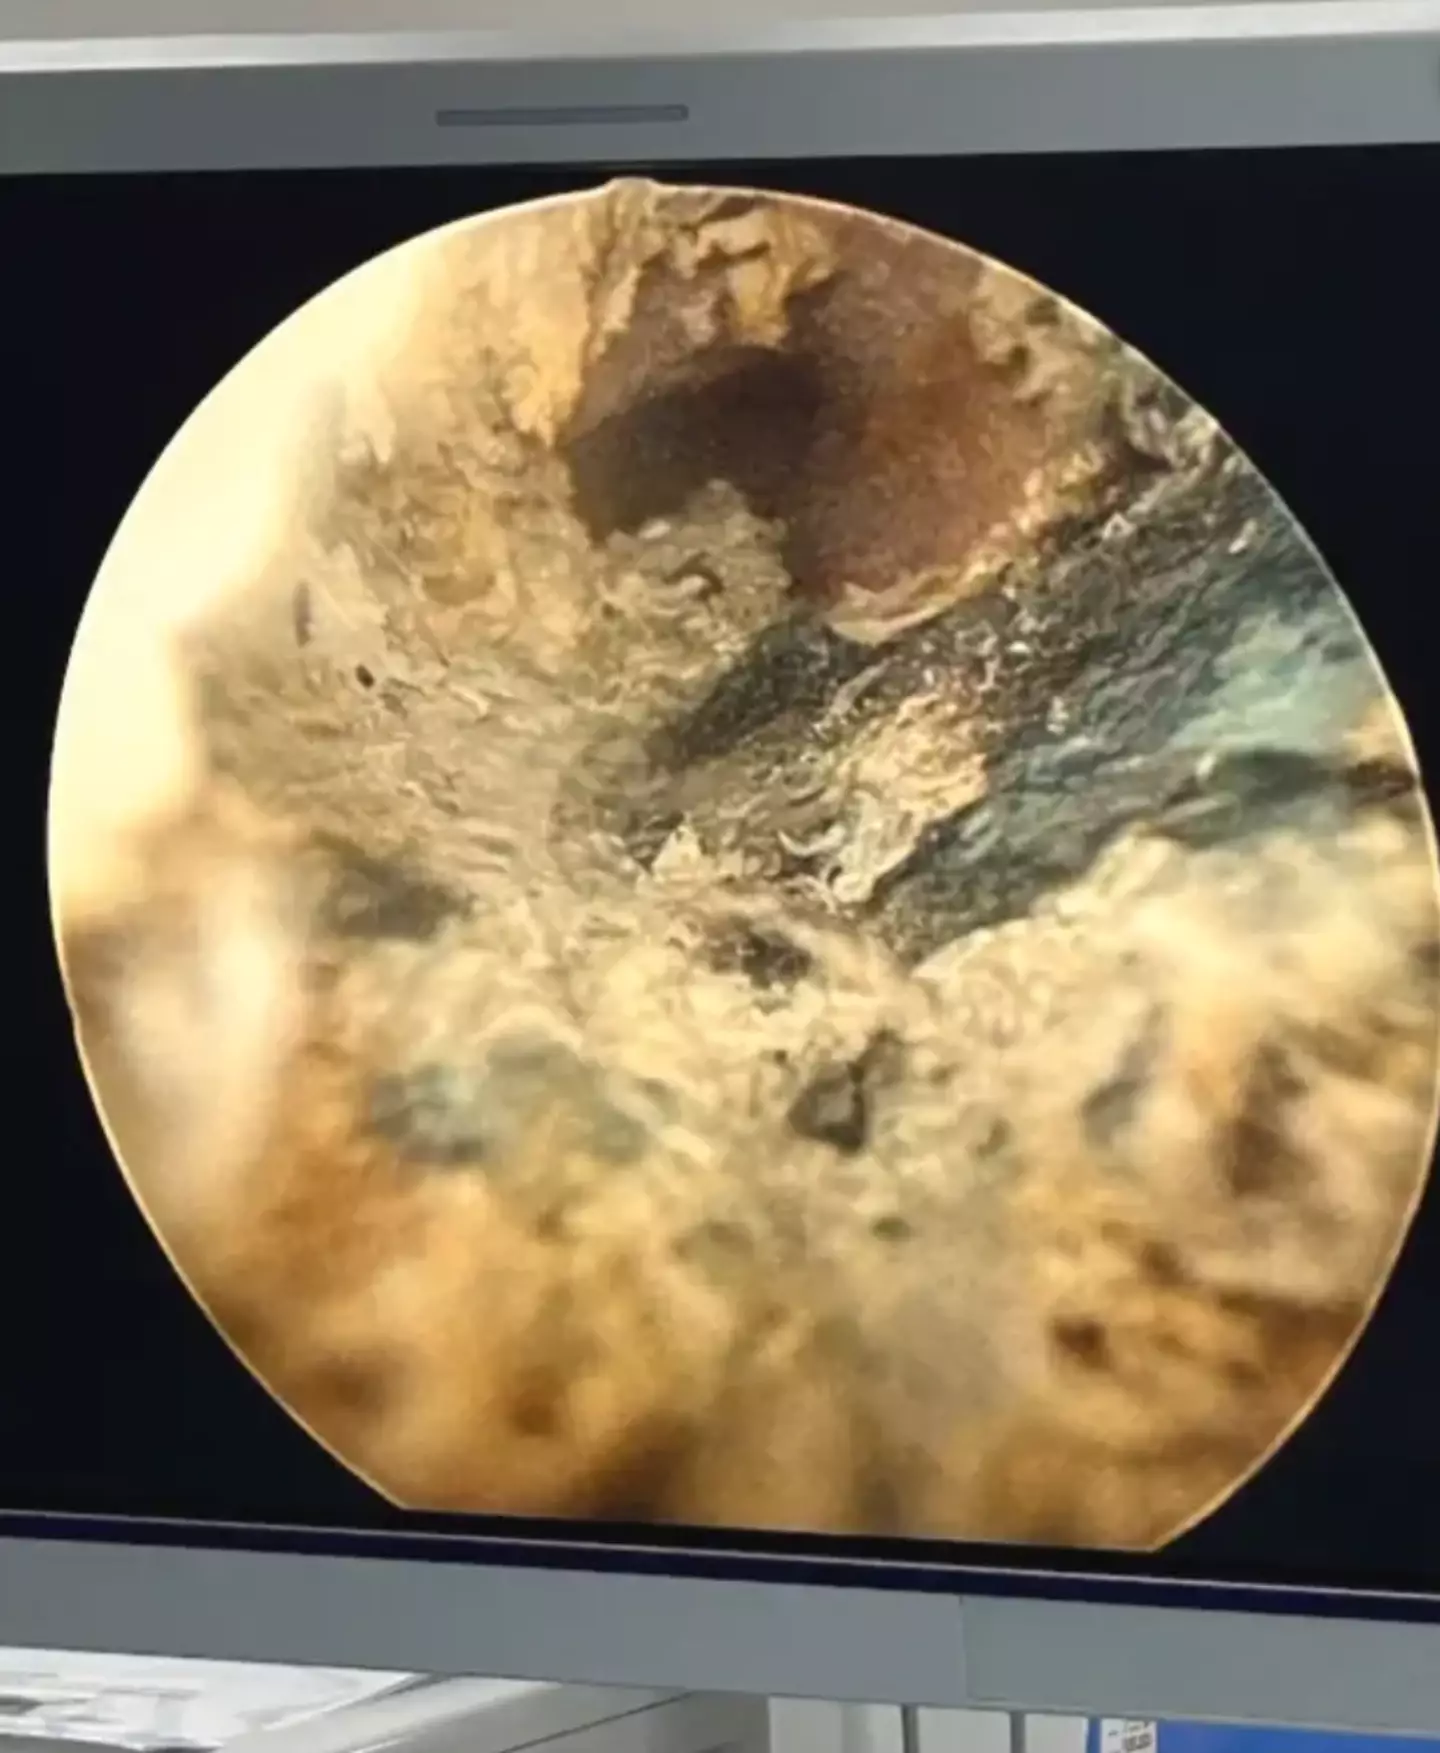

"All extracted batteries were coated with black tar-like material," the study noted.

The doctors discovered the man developed an 'extensive degree of necrosis' - subsequently meaning part of his urethra had to be removed.

"Given the complexity of his injury, it was deemed that formal penile urethral reconstruction would likely require a 3-stage repair," the researchers added.